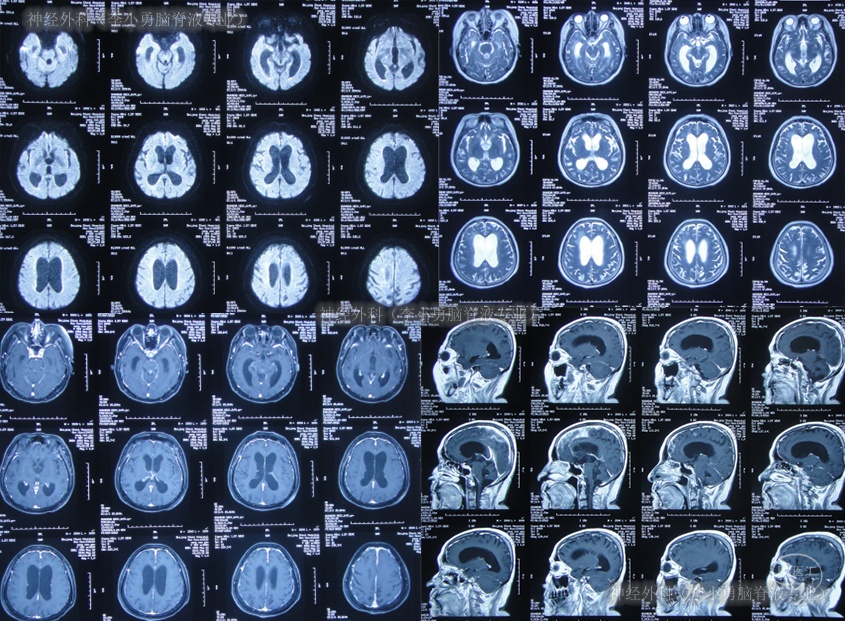

又过2月后即2011年10月14日,夜里2点起夜时突然站不稳,再次出现头昏,呕吐频繁,四肢无力,2011年10月17日第2次就诊于第2家医院:呼和浩特市某医院神经内科住院治疗,行头颅MRI(图-1)认为“末梢神经脱髓鞘病变,考虑为格林巴利综合征,轻度脑积水”。

图-1:2011年11月17日头颅核磁